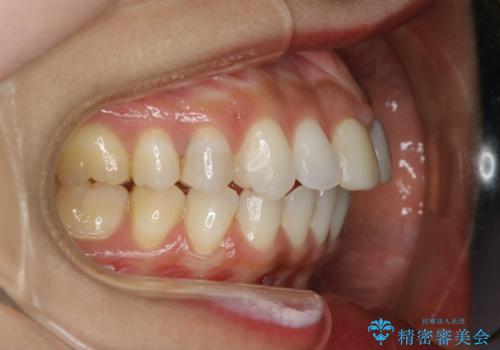

すきっ歯を治したい。インビザライン・ライトによる矯正治療

- 正中離開を気にされて来院された患者様です。

インビザラインでの治療を希望され、正中離開のみ治したいとのことだったので、インビザライン・ライト(片顎)での治療を選択しました。

インビザライン・ライトは枚数が少ないため歯の移動量に限界がありますが、短期間での治療が可能です。